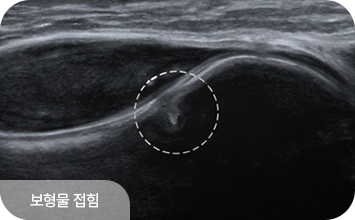

유방 확대술(보형물 삽입) 후에도 초음파 검진은 동일하게 시행할 수 있으며,

보형물 위의 유방 조직을 꼼꼼히 관찰하여 종괴나 이상 소견을 확인합니다.

보형물 자체의 파열이나 누출 여부도 초음파로 평가할 수 있어,

수술 후에도 정기적인 초음파 검진이 중요합니다.